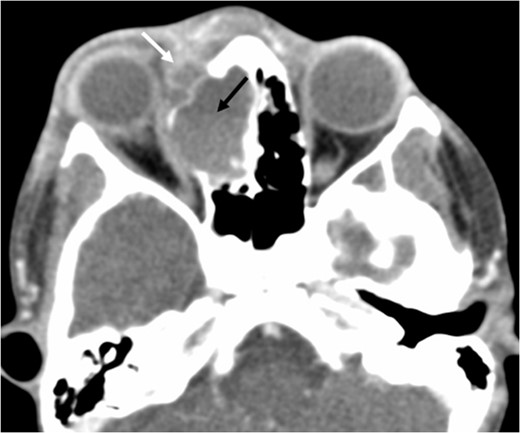

A 6-year-old boy with a background of asthma presented to a tertiary paediatric unit in May 2016 with a 3-day history of right eye pain, proptosis and erythema under the care of the ENT team. A provisional diagnosis of a periorbital cellulitis was made secondary to ethmoid sinusitis and management with intravenous antibiotics (ceftriaxone), intranasal steroids, saline douches and topical oxyxlometazoline was initiated. Ophthalmological assessment demonstrated normal colour vision, acuity and light reflexes bilaterally but also proptosis-related ophthalmoplegia. Computed tomography (CT) imaging of the orbits and paranasal sinuses demonstrated complete opacification of the right-sided paranasal sinuses and compromise of the right frontal and ostiomeatal unit. In addition there was an expansile abnormality centred on the ethmoidal labyrinth with bony remodelling of the lamina papyracea and a subperiosteal collection adjacent to the medial orbital wall (Figs 1 and 2). The most likely diagnosis was felt to be an infective process with mucopyocele formation complicated by a subperisoteal post-septal collection. An MRI scan with gadolinium of the orbits and sinuses confirmed the unilateral pattern of sinus opacification within the right frontal, ethmoids and maxillary sinus. The lesion demonstrated multiple fluid–fluid levels and peripheral enhancement (Figs 3 and 4). The patient was treated by endoscopic drainage of the lesion, which revealed only blood. He initially had some improvement of his proptosis but recurred within a few days and so further, more extensive endoscopic debridement was performed.

Axial post-contrast CT demonstrating the peripherally enhancing right-sided intra-orbital subperiosteal component. The expansile lesion centred on the right ethmoidal labyrinth demonstrates a faint fluid–fluid level.